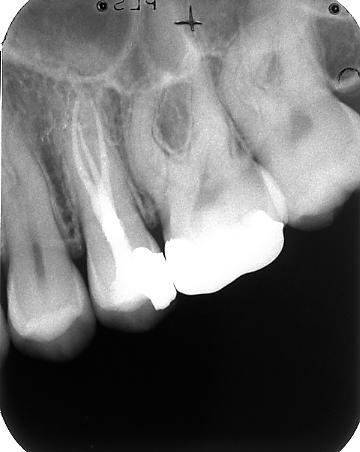

Diepe wortelsplitsingen zoals met enige regelmaat voorkomen bij onder en bovenpremolaren zijn vaak al te diagnosticeren door de tandfilm nauwkeurig te bekijken. Als een wortelkanaal ergens halverwege de radix plotseling niet meer zichtbaar is op de röntgenfoto wijst dat op een diepe wortelsplitsing.